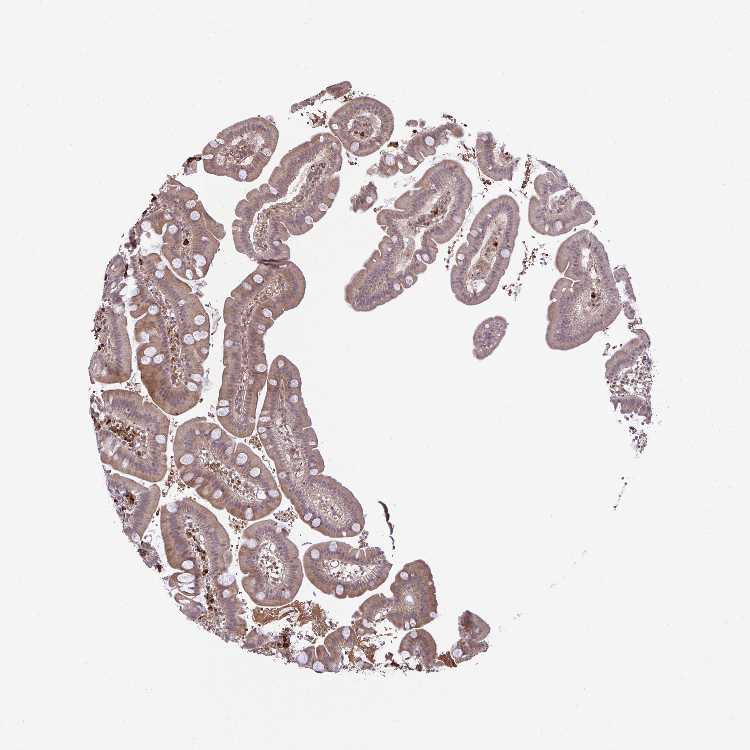

SMALL INTESTINE - Antibody stainingi

Antibody staining in the annotated cell types in the current human tissue is reported as not detected, low, medium, or high, based on conventional immunohistochemistry profiling in selected tissues. This score is based on the combination of the staining intensity and fraction of stained cells.

Each image is clickable and will lead to virtual microscopy that enables deeper exploration of all samples and also displays staining intensity scores, fraction scores and subcellular localization as well as patient and tissue information for each sample.

Antibody HPA054512Antibody HPA059951

Glandular cells MediumHigh